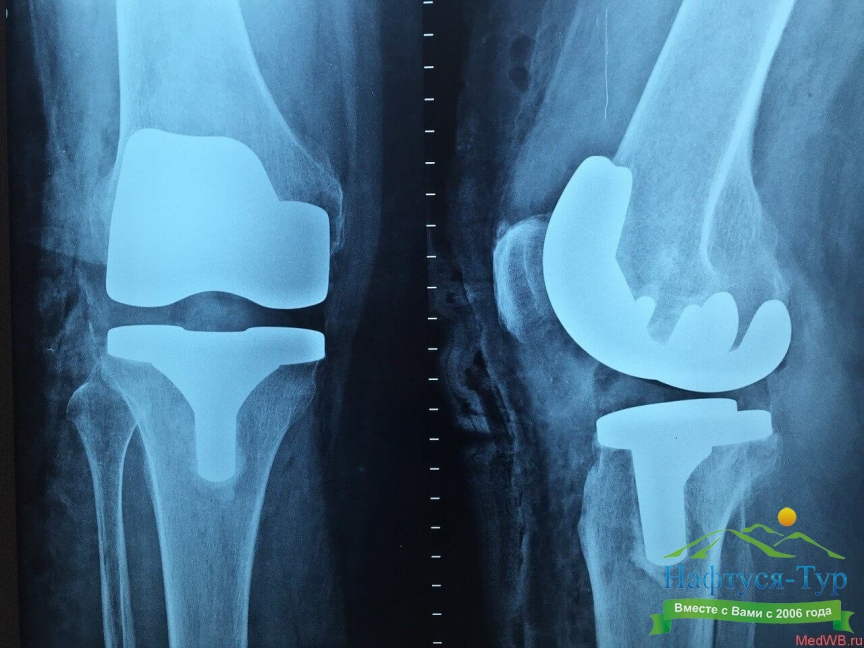

Рентген – упрощенное название неинвазивных диагностических методов, официально называемых рентгенография, рентгенологическое исследование. За счет использования рентгеновских лучей, которые проходят через тело человека, медики могут получить картину внутренних тканей и органов, определить имеющиеся патологии. В зависимости от назначений диагноста рентгенологическое исследование может проводиться в различных формах – обзорное, флюорография, ангиография, урография и так далее. Результаты исследований позволяют выявлять патологии костей, суставов, полых органов, отложения солей, скопления газов и жидкостей.Кабинет рентгенографии сегодня имеется практически в каждом санатории нашей страны. При этом многие здравницы располагают самыми современными рентгеновскими установками, управляемыми компьютером. За счет обработки данных в памяти компьютера и представления изображений в цифровой форме достигается более высокое качество диагностики, что в свою очередь позволяет проводить более эффективное лечение.